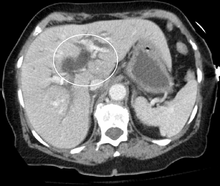

Post-hepatic jaundice, also called obstructive jaundice, is caused by an interruption to the drainage of bile containing conjugated bilirubin in the biliary system. The most common causes are gallstones in the common bile duct, and pancreatic cancer in the head of the pancreas. Also, a group of parasites known as "liver flukes" can live in the common bile duct, causing obstructive jaundice. Other causes include strictures of the common bile duct, biliary atresia, cholangiocarcinoma, pancreatitis, cholestasis of pregnancy, and pancreatic pseudocysts. A rare cause of obstructive jaundice is Mirizzi's syndrome.